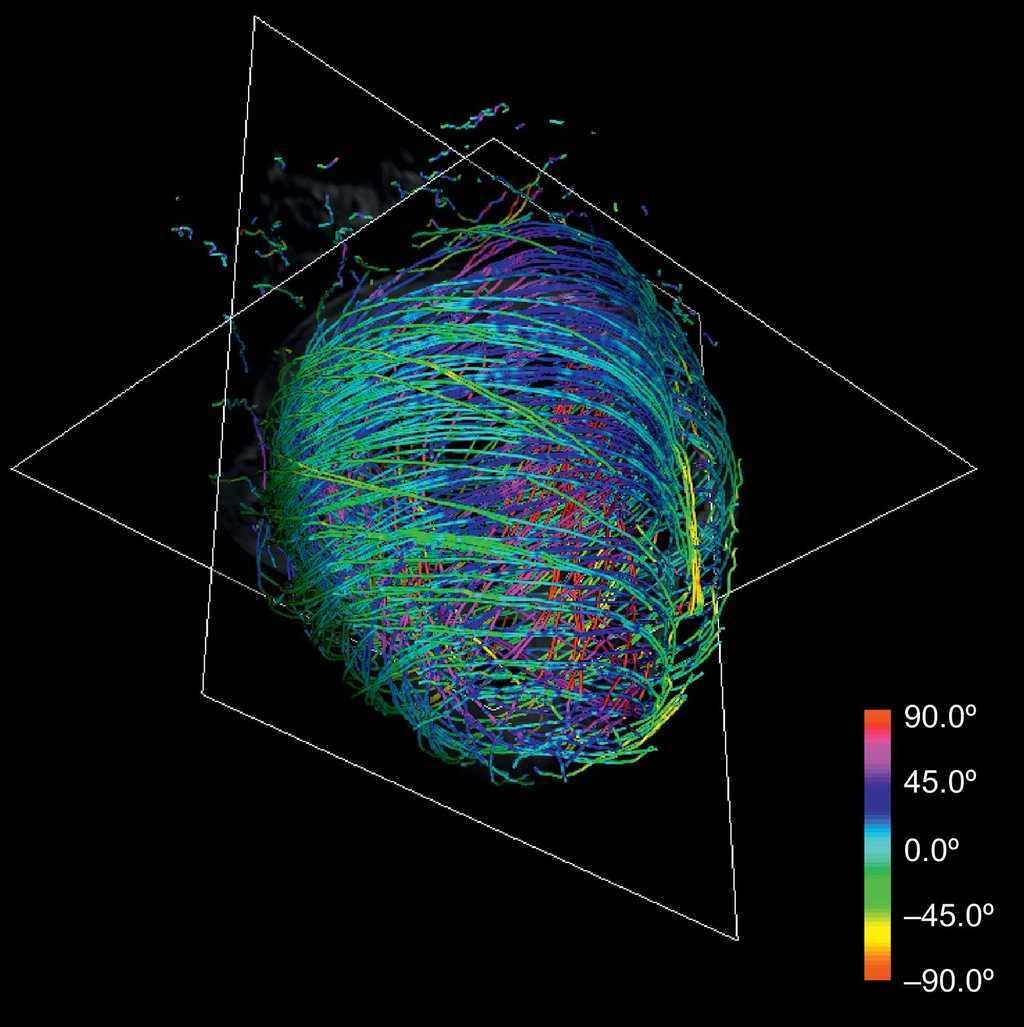

modernste Bildgebung (experimentell)

- 3D-Analyse Myokardarchitektur im Diffusions-Tensor-MRT

- Nachweis einer spiralförmigen Myokardfaseranordnung

- Farbschema stellt die Faserorientierungen dar